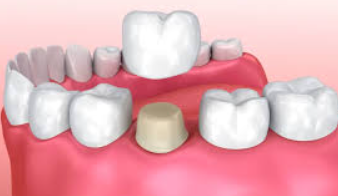

Fractured jaws may require open reduction surgery, jaw wiring for immobilization, and dental crowns and braces to restore a normal bite. Lacerations may need suturing.